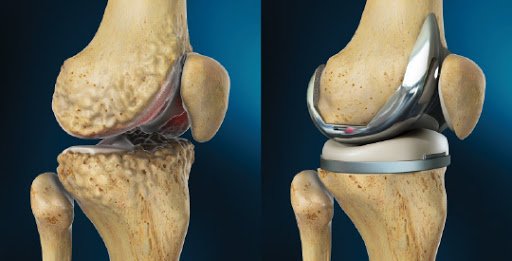

Knee

Replacement

Advanced knee replacement procedures for pain-free mobility and joint function.